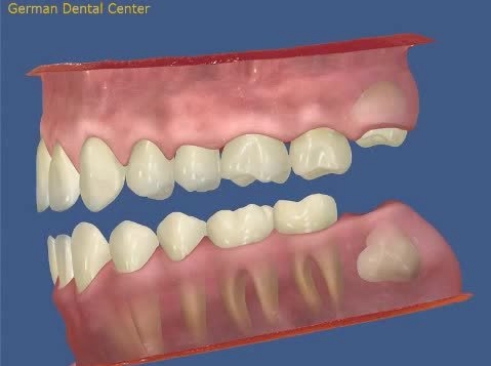

- Исправление прикуса